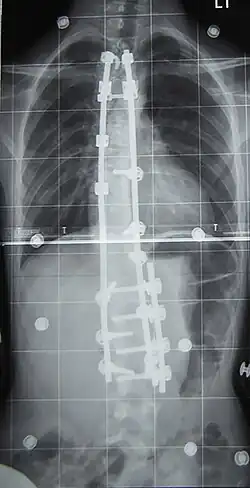

Preoperative (left) and postoperative (right) X-ray of a person with thoracic dextroscoliosis and lumbar levoscoliosis: The X-ray is usually projected anteroposterior, such that the right side of the subject is on the right side of the image; i.e., the subject is viewed from the rear (see left image; the right image is seen from the front). This projection is typically used by spine surgeons, as it is how surgeons see their patients when they are on the operating table (in the prone position). This is the opposite of many Chest radiographs, where the image is posteroanterior, i.e., projected as if looking at the patient from the front. The surgery was a fusion with instrumentation.

Surgery is usually recommended by orthopedists for curves with a high likelihood of progression (i.e., greater than 45–50° of magnitude), curves that would be cosmetically unacceptable as an adult, curves in people with spina bifida and cerebral palsy that interfere with sitting and care, and curves that affect physiological functions such as breathing.[104][105]

Surgery is indicated by the Society on Scoliosis Orthopaedic and Rehabilitation Treatment (SOSORT) at 45–50°[4] and by the Scoliosis Research Society (SRS) at a Cobb angle of 45°.[106] SOSORT uses the 45–50° threshold as a result of the well-documented, plus or minus 5° measurement error that can occur while measuring Cobb angles.[106]

Surgeons who specialize in spine surgery perform surgery for scoliosis. To completely straighten a scoliotic spine is usually impossible, but for the most part, significant corrections are achieved.[107]

The two main types of surgery are:[108]

• Anterior fusion: This surgical approach is through an incision at the side of the chest wall.

• Posterior fusion: This surgical approach is through an incision on the back and uses metal instrumentation to correct the curve.

One or both of these surgical procedures may be needed. The surgery may be done in one or two stages and, on average, takes four to eight hours.